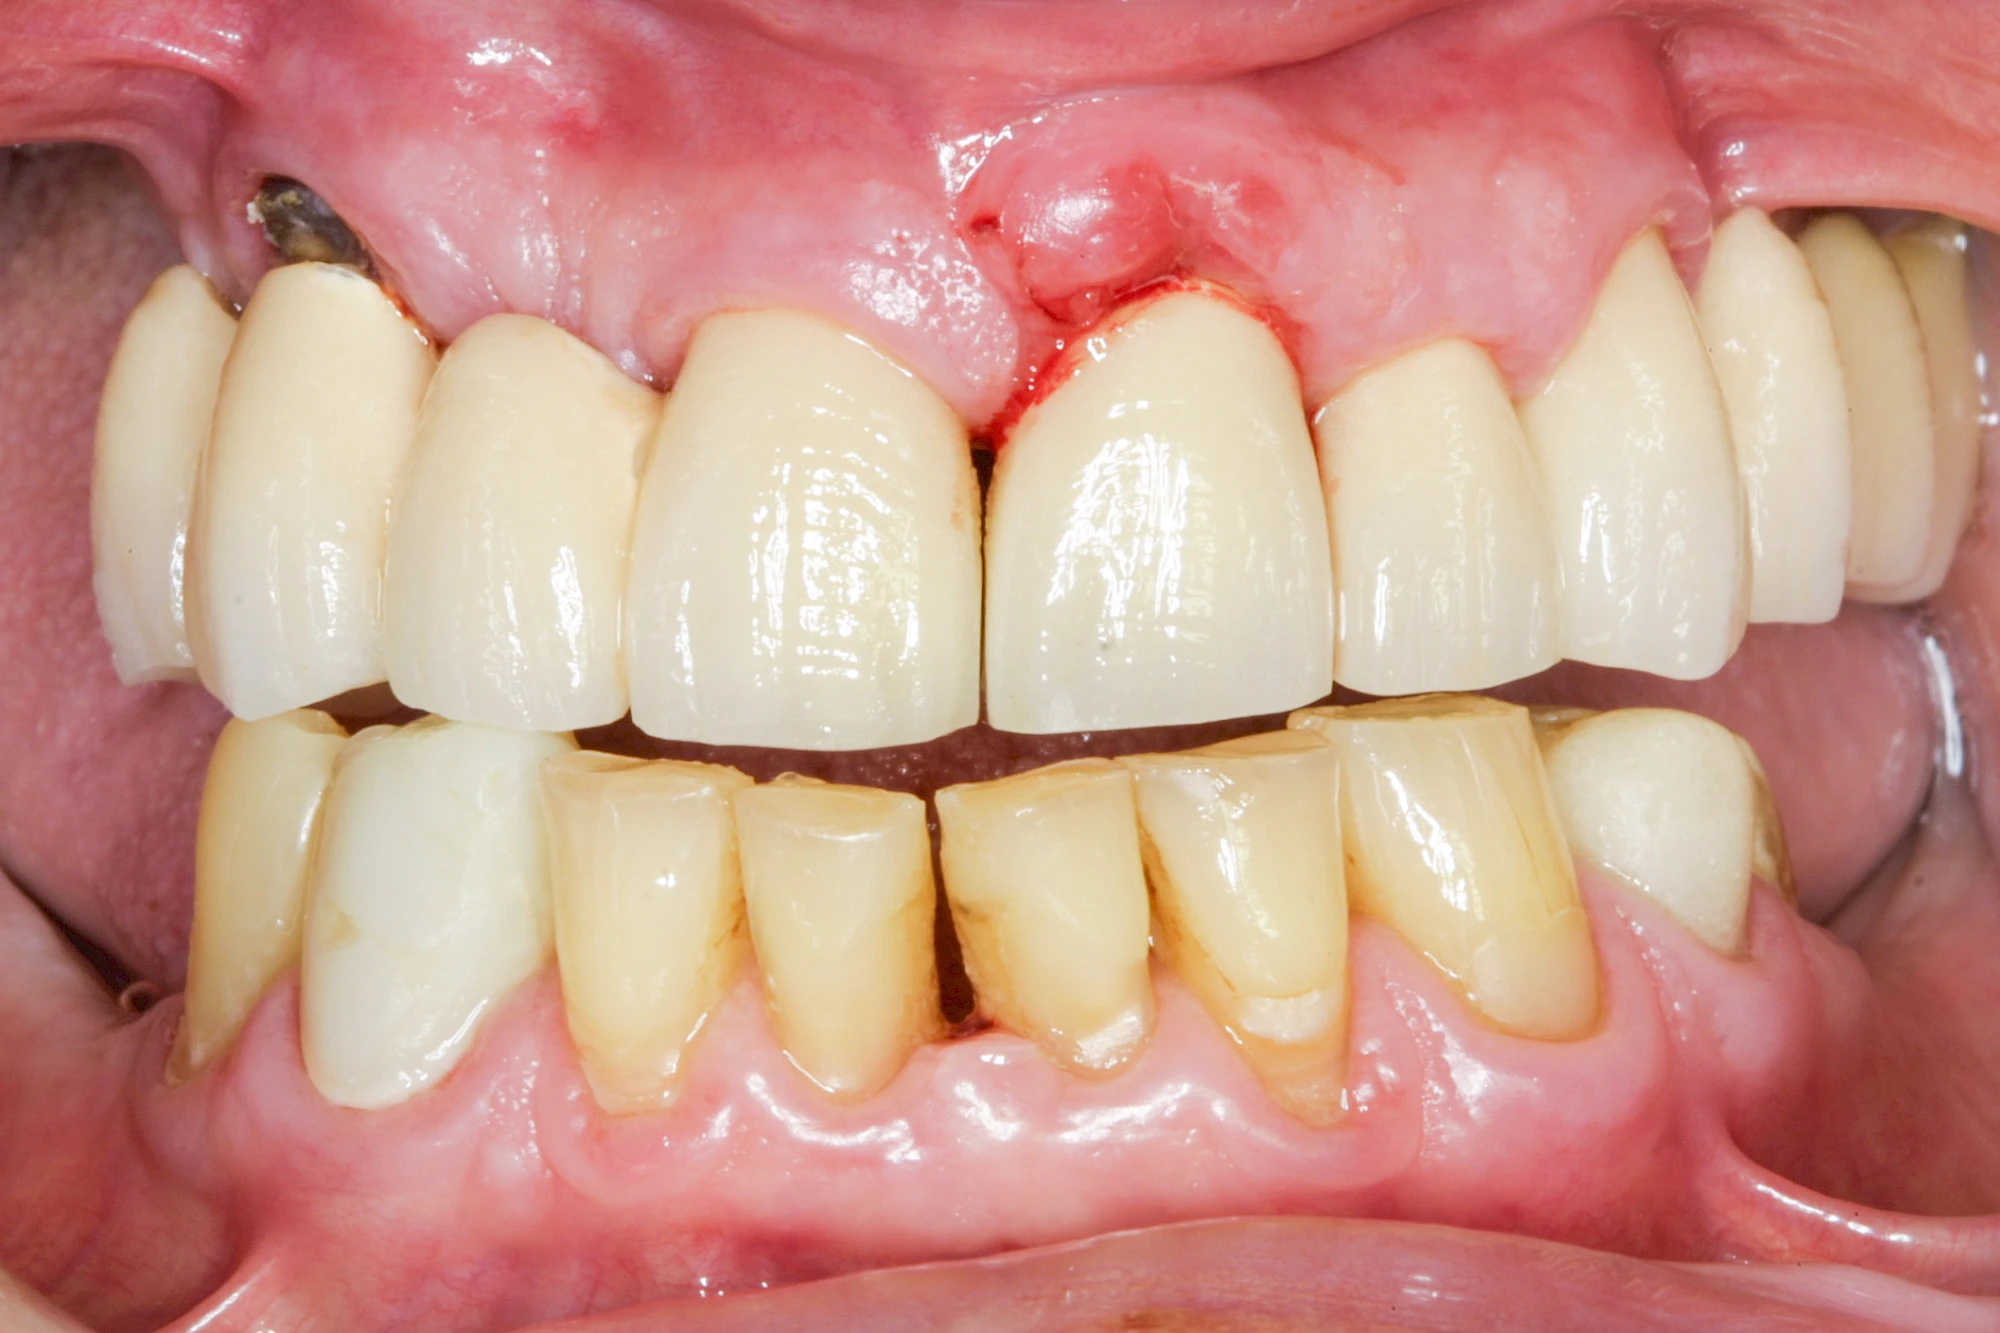

Sonderform: Fistel

Bei einer Fistel hat sich meist eine Entzündung (manchmal auch Erreger selbst) z. B. aufgrund von Karies oder aufgrund eines Unfalls über den Zahnnerv und die Wurzelspitze (Apex) in den umliegenden Knochen ausgebreitet (apikale Parodontitis) und schnell einen Weg durch den umgebenden Knochen und die aufliegende Schleimhaut in die Mundhöhle gebahnt.

Fisteln sind in der Regel nicht schmerzhaft und fallen häufig als kleine Öffnung weiter entfernt vom Zahnfleisch nahe der Umschlagfalte auf. Aus der Fistelöffnung entleert sich spontan gelbliches Sekret (Eiter) oder es lässt sich mit dem Finger ausstreichen. Manchmal beschreiben die betroffenen Menschen immer wieder einen komischen Geschmack im Mund.

Im fortgeschrittenen Stadium kann die Schleimhaut sich weiter zurückgezogen haben und die Wurzelspitze sichtbar sein. In der Regel treten bei Fisteln keine Schwellungen auf, weil sich die Entzündung nicht im Gewebe ausbreitet.